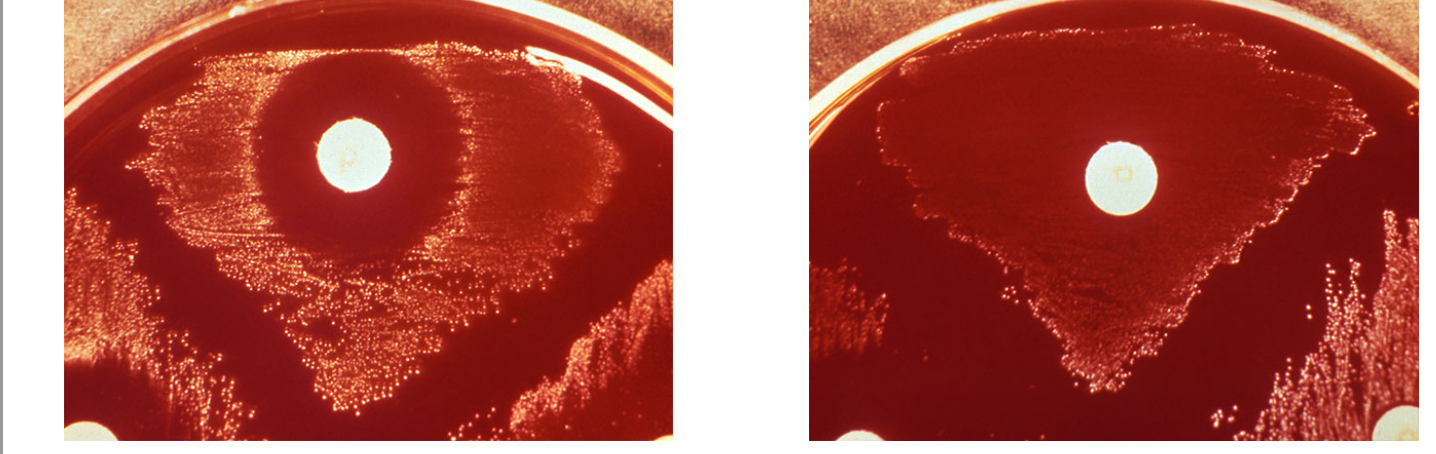

blood agar hemolysis shows growth and alpha hemolytic

The blood agar hemolysis test grows bacteria with fastidious conditions and also differentiates between bacterial hemolysis of RBCs by visualization. Here are the results of your blood agar hemolysis test. What can you conclude?

zone of inhibition, sensitive to optochin

After incubation with an optochin disc, you observe the plate results. Your plate is shown at the left with a control plate on the right. What can you conclude?